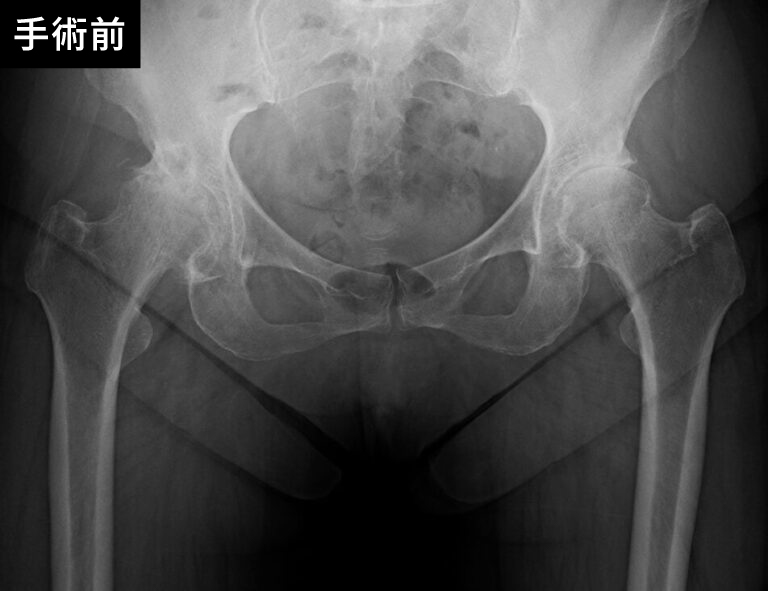

股関節の手術前後

手術の種類には、関節全体を置き換える「全人工関節置換術」と、一部のみを置き換える「部分人工関節置換術」があり、患者さまの症状や状態に応じて選択されます。当院では、専門医が最新の技術を駆使して安全で精密な手術を行い、術後の回復を最大限にサポートします。